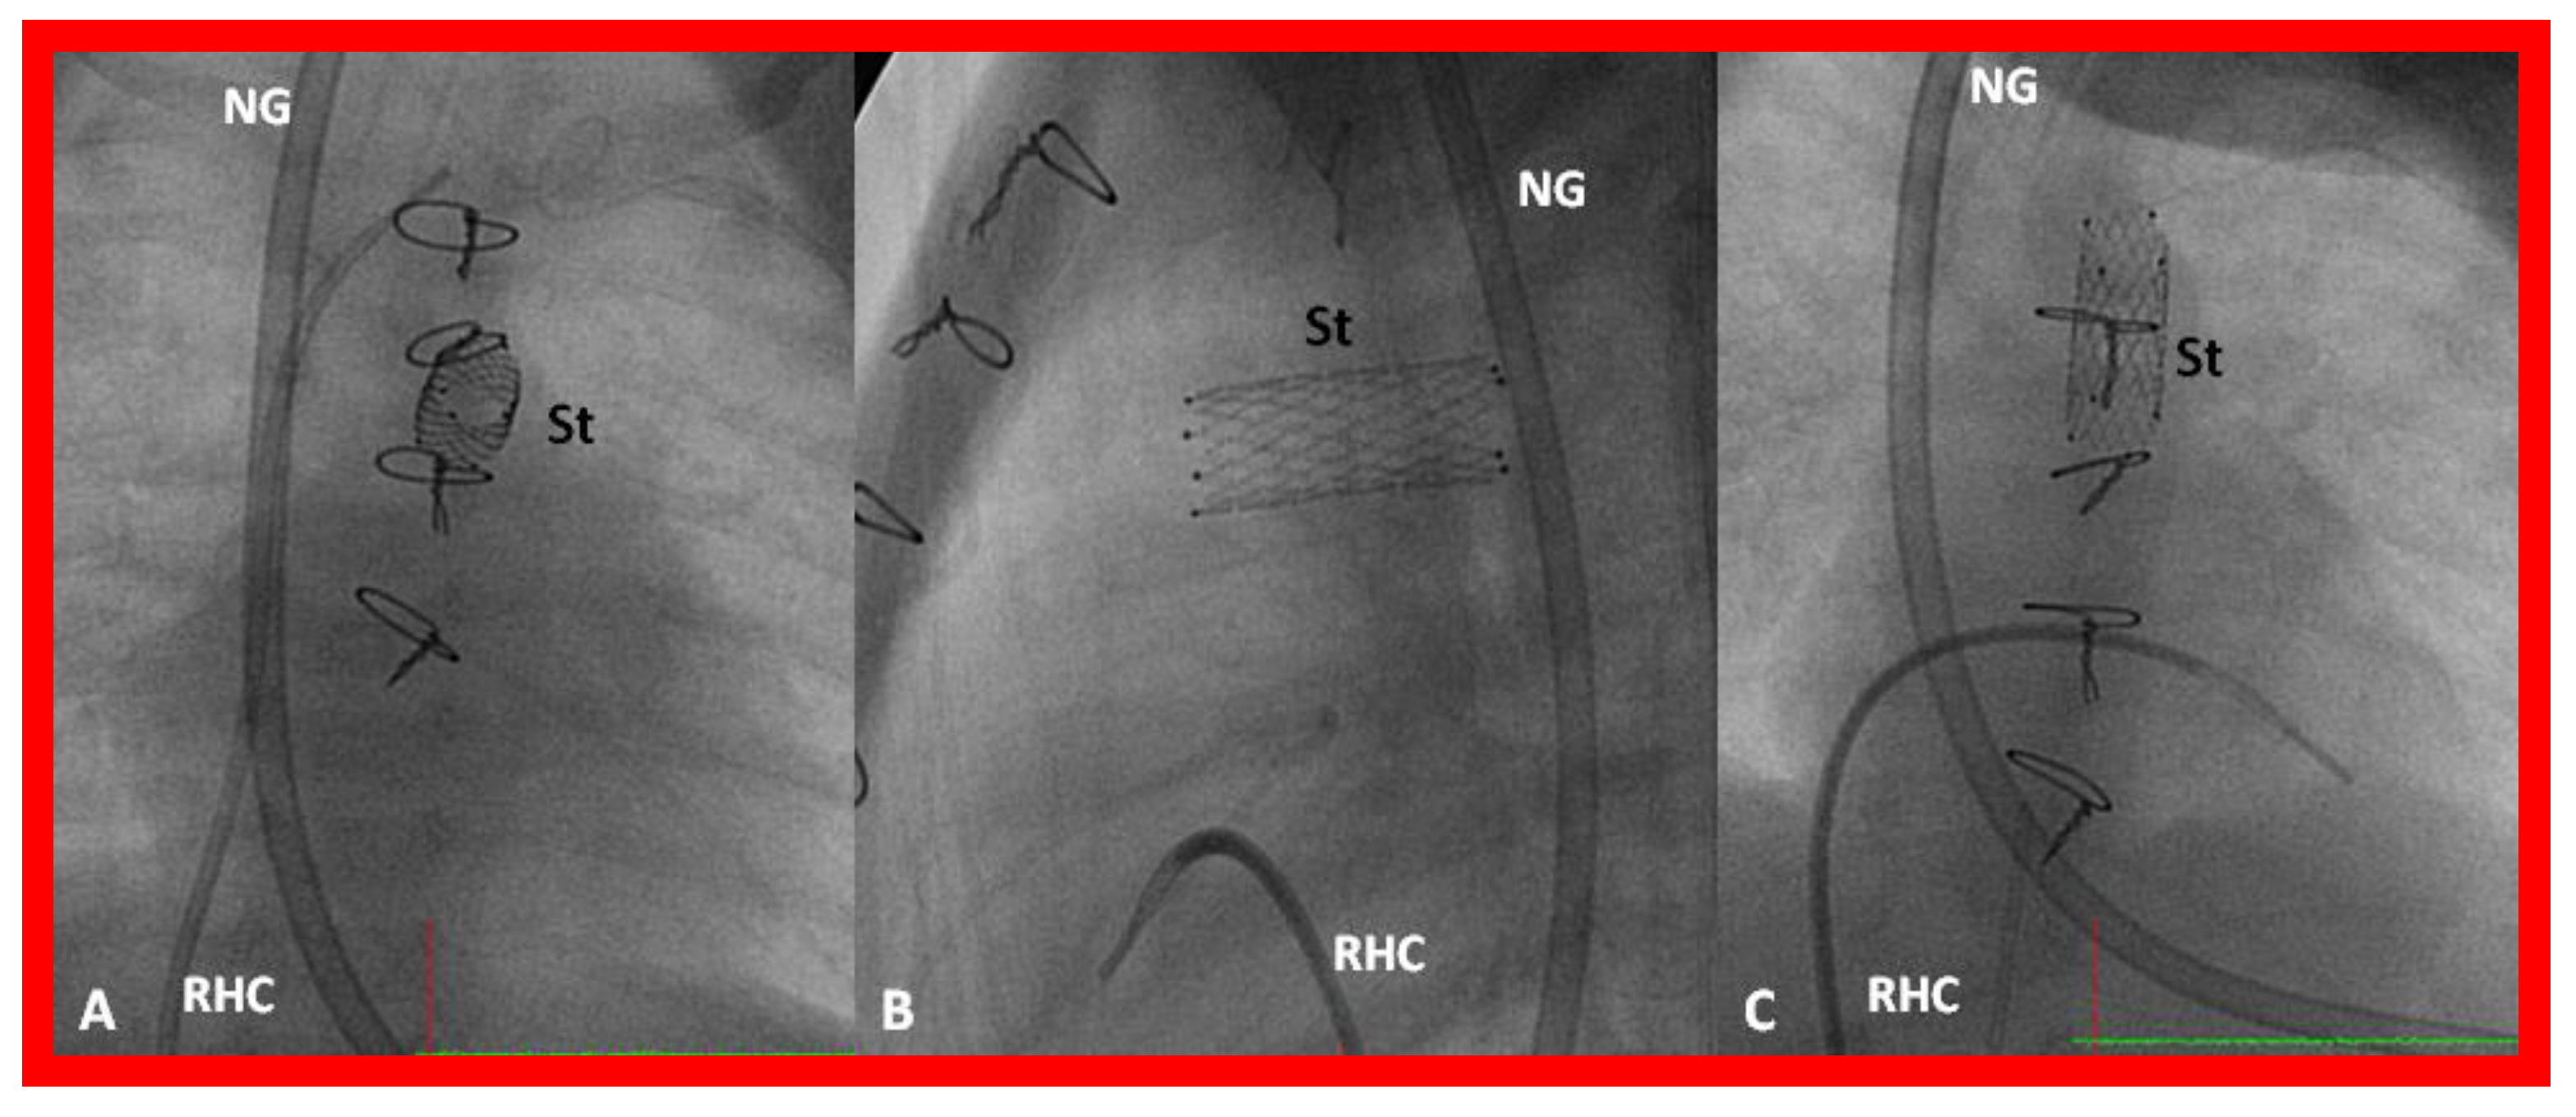

- Rao, P.S.; Balfour, I.C.; Singh, G.K.; Jureidini, S.B.; Chen, S. Bridge stents in the management of obstructive vascular lesions in children. Am. J. Cardiol. 2001, 88, 699–702. [Google Scholar] [CrossRef]

- Rao, P.S. Stents in the management of congenital heart disease in the pediatric and adult patients. Indian Heart J. 2001, 53, 714–730. [Google Scholar] [PubMed]

- Sahu, R.; Rao, P.S. Transcatheter stent therapy in children: An update. Pediatrics Ther. 2012, S5. [Google Scholar] [CrossRef]

- Rao, P.S. Stents in the Management of Vascular Obstructive Lesions Associated with Congenital Heart Disease. In Cardiac Catheterization and Imaging (From Pediatrics to Geriatrics); Vijayalakshmi, I.B., Ed.; Jaypee Publications: New Delhi, India, 2015; pp. 573–598. [Google Scholar]

- Rao, P.S. Stents. In Pediatric Cardiology: How It Has Evolved Over The Last 50 Years; Rao, P.S., Ed.; Cambridge Scholars Publishing: New Castle upon Tyne, UK, 2020; pp. 511–559. ISBN 9781527548886. [Google Scholar]